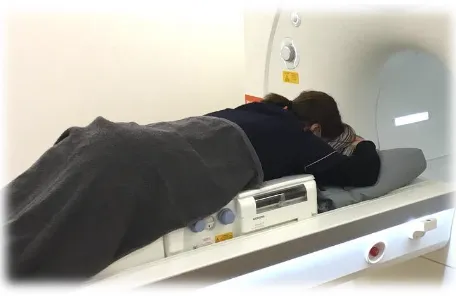

乳房MRIアトラス | 五味 直哉, 菊池 真理, 五味 直哉, 菊池 真理。乳房MRIアトラス 裁断済 書き込みなし 乳腺MRI。乳房MRIアトラス 裁断済 書き込みなし 乳腺MRI 本。人気アルファ米5種セット 25袋。婦人科MRIアトラス 改訂第2版 (画像診断 別冊KEYBOOKシリーズ。乳房MRI撮影・読影の基礎とコツ (臨床画像 38巻10号) | 医書.jp。乳房MRI | 那珂川市の病院ならCT・MRI検査が可能な吉田。ご覧いただきありがとうございます!専用の機械で裁断してありますが、素人裁断のものです。1ページずつバラバラになってます。裁断済みである事がご理解いただける方のみ購入してください。『裁断済み』のため状態を『傷や汚れあり』にしていま「乳房MRIアトラス」五味 直哉 / 菊池 真理 / 菊池 真理定価: ¥ 9200#五味直哉 #五味_直哉 #菊池真理 #菊池_真理 #菊池真理 #菊池_真理 #本 #自然/医療・薬学・健康。MRI-乳腺MRIの質と安全性を向上させるSmartExam Breast-技術。乳房MRI検査 獨協医科大学埼玉医療センター 放射線部。乳房MRI造影以外のシーケンスの活用法 (臨床画像 38巻10号。乳房MRIアトラス | 五味 直哉, 菊池 真理, 五味 直哉, 菊池 真理。BI-RADSを克服する・Mass編【造影乳房MRIを読めるようになる。乳腺MRI検査・検診 – AIC八重洲クリニック 乳腺外科